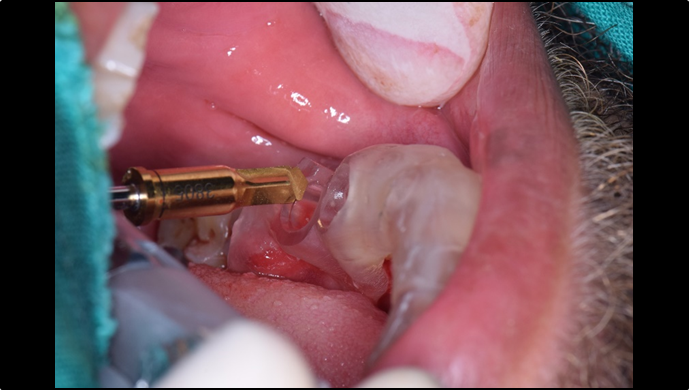

“ One implant /One tooth/ One hour step-by-step

+ associated connective graft ”

Clinical case: EImmediate implant placement & loading of #35 extraction socket with defect

- Courtesy of Dr. Kwang Bum Park, Korea -

Dr. Laurent Sers, immediate loading, digital guided surgery, digital ONE-DAY implant, maxillary anterior, #21, guided surgery, immediate loading, AnyRidge, R2GATE, Mega ISQ, R2GATE Full Surgical Kit

implant system, R2GATE Guide, R2GATE surgical kit (AnyRidge), Mega ISQ